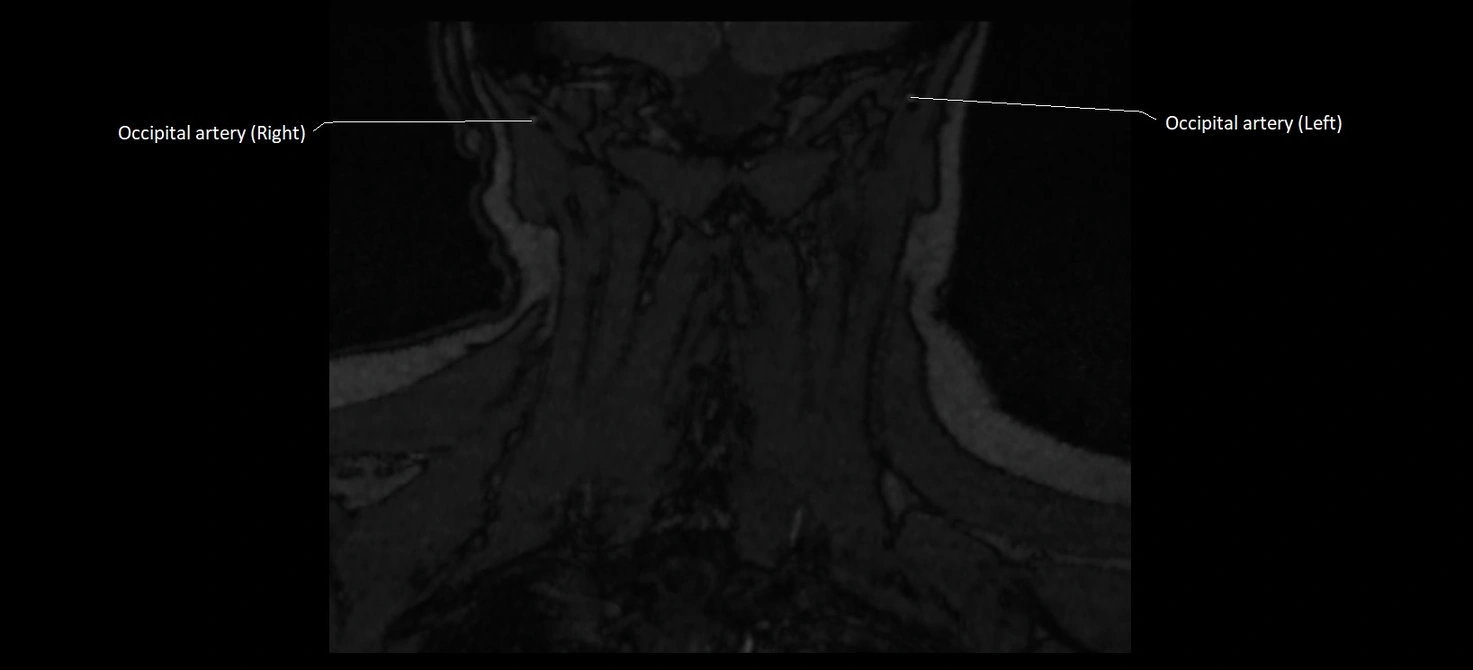

MRI images

image